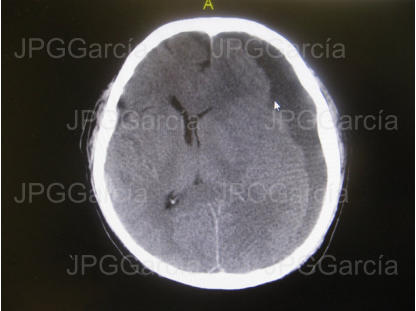

Estudio tomográfico postquirúrgico